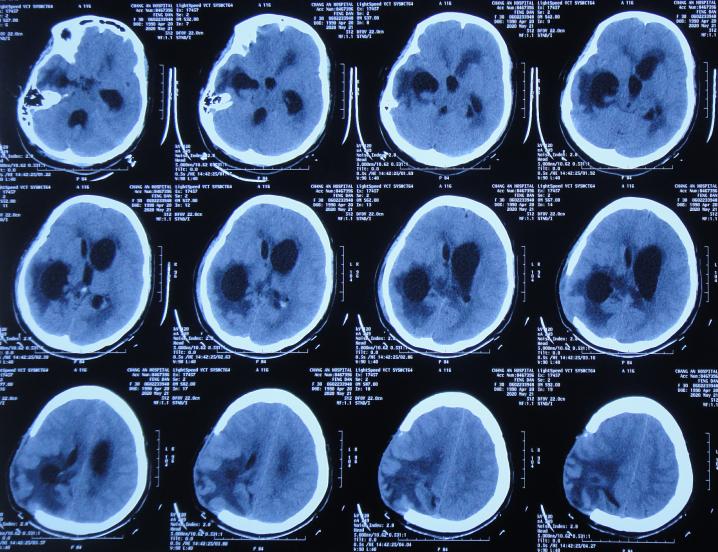

患者于2020年4月2日,在公司上班时突发头痛呕吐,急诊至陕西省西安市某二级医院,急诊查头颅CT检查示右顶叶脑出血破入脑室( 图-1 ),全脑血管造影示脑血管畸形(片子丢失);进行了开颅脑血管畸形切除术+去骨板减压术,术中留置引流外管;术后当天转入ICU继续治疗。

图-1: 2020年4月2日头颅CT